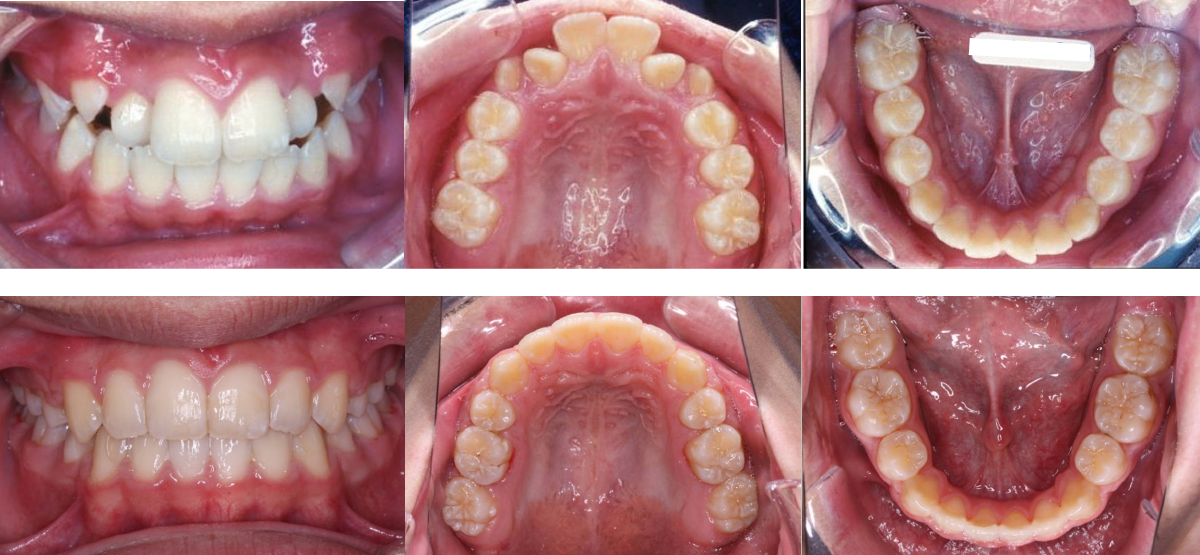

④叢生(でこぼこ)の矯正治療例(10代男性・治療期間1年7か月)

| 年齢・性別 | 10代男性 |

| 治療期間 | 1年7か月 |

| 抜歯 | 上2本、下2本(小臼歯) |

| 治療費 | 90万円(調整費、保定費まで含む総額制) |

| 備考 | 裏側矯正 |

| リスク・副作用 | 痛み・治療後の後戻り・歯根吸収・歯髄壊死・歯肉退縮 |